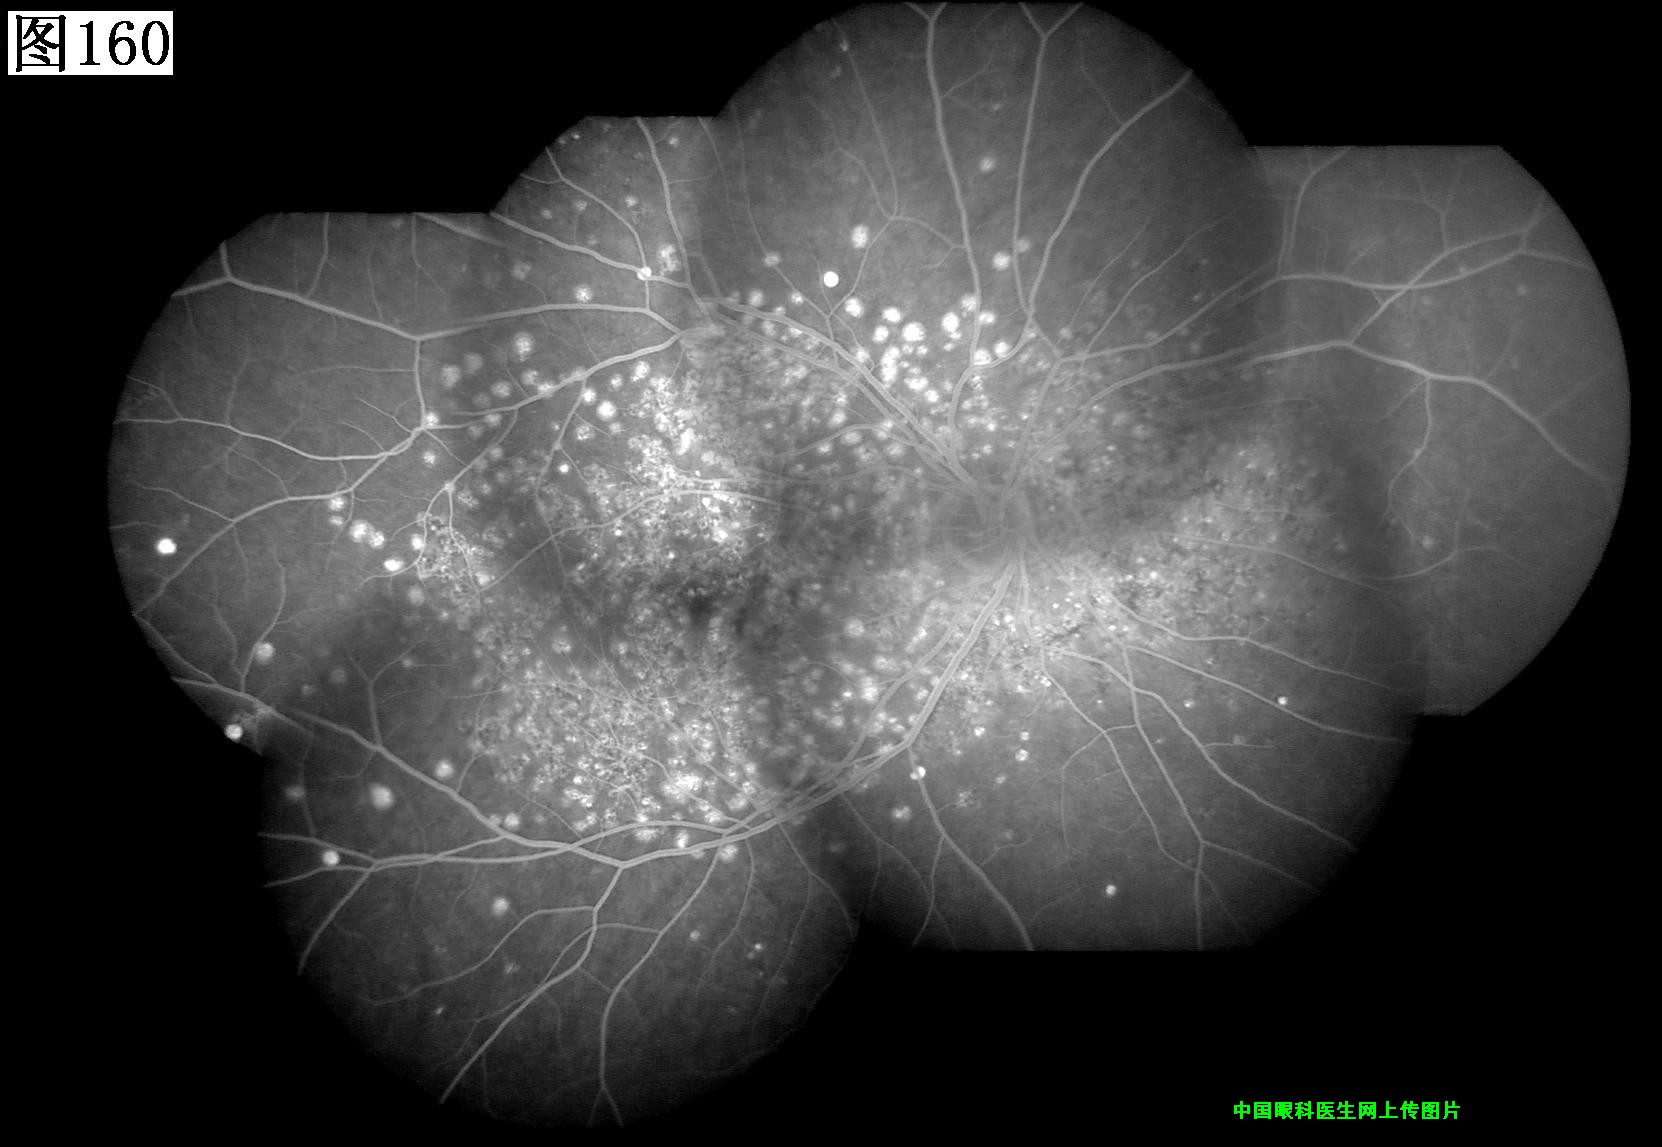

157 158 159 160